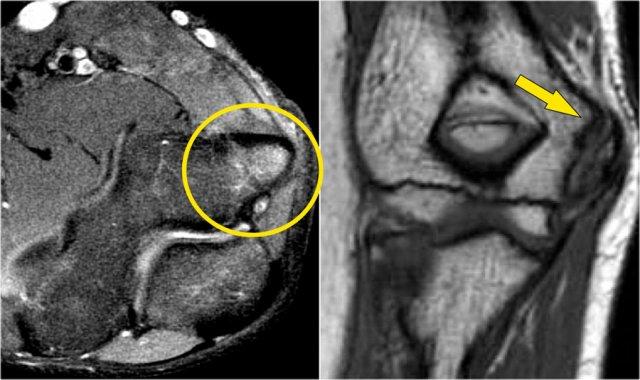

Arthrosis in valgus overload syndrome

Do quá tải valgus, có các lực cắt tác động lên phần sau-trong của khớp cánh tay-trụ.

Lưu ý tình trạng xơ cứng dưới sụn được thấy trên ảnh T1W (mũi tên đỏ).

Trên hình ảnh T2W có phù tủy xương dưới sụn và mất sụn khớp (mũi tên vàng).

Đây là hình ảnh của một vận động viên bóng chày 20 tuổi.

Trên các hình ảnh mặt phẳng coronal, bó trước của dây chằng UCL hiện rõ đẹp, nhưng lưu ý rằng có sự hình thành gai xương ở phần trong của khớp (mũi tên đỏ).

Khi chúng ta đi xa hơn về phía sau có một vùng nhỏ có tín hiệu thấp (mũi tên vàng), đây là một chỗ bong gân của một phần dây chằng bên trụ (UCL).

Điều này được thể hiện rõ hơn trên phim X-quang.

Continue with the axial scan.

Khi quan sát trên lát cắt ngang (axial), chúng ta có thể nhận thấy sự hình thành gai xương khổng lồ.

Lưu ý rằng dây thần kinh trụ (mũi tên màu xanh) nằm cạnh các gai xương này và những bệnh nhân này có thể biểu hiện bệnh lý thần kinh trụ.